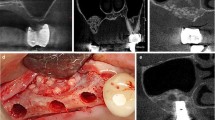

Bilateral maxillary sinus augmentation was performed with lateral window approach as described by Tatum [19]. In this split-mouth study, right and left sinus sites were randomly assigned to test and control group. The sinus was grafted with hyaluronic matrix (HyalossTM matrix, ANIKA Therapeutics, Italy) and CHBG (Apatos mix, OsteoBiol®, Italy) in test group and only with CHBG in control group. Hyaluronic matrix, in the form of fibers, consists of esterified bacterial origin HA. It immediately takes gel form in contact with sterile saline (Fig. 1).

Four months after augmentation, during implant placement, 26 bone samples were taken from the grafted sinus areas with a 2-mm-diameter trephine bur. After removal, these samples were placed in 10% neutral buffered formalin solution.

Bone samples were fixed to the scanner compartment of the microCT device (Skyscan 1174, Skyscan, Kontich, Belgium) via patafix. After the area setting of 800 µA, 50 kV, and 40.89 µm pixel size was arranged and saved, each sample was scanned with the same setting. The rotation step of microCT was set at 0.7° and the sample was determined to perform 180° rotation scan with 2300 ms exposure. Raw data were obtained during scanning and subsequent reconstructions of these data were carried out with the software NRecon (NRecon version 1.6.9.4, Skyscan, Kontich, Belgium), provided by the manufacturer. During reconstruction beam hardening, ring artifact reduction, smoothing, and frame averaging were individually adjusted to the optimum value for each sample. As a result of the reconstruction of the raw data, 8-bit gray value images were obtained. Reconstructed images were transferred to CTAn (version 1.13.5.1) software. Using CTAn scan, region of interest (ROI) was drawn within the sample to analyze the 3D microarchitecture of each sample.